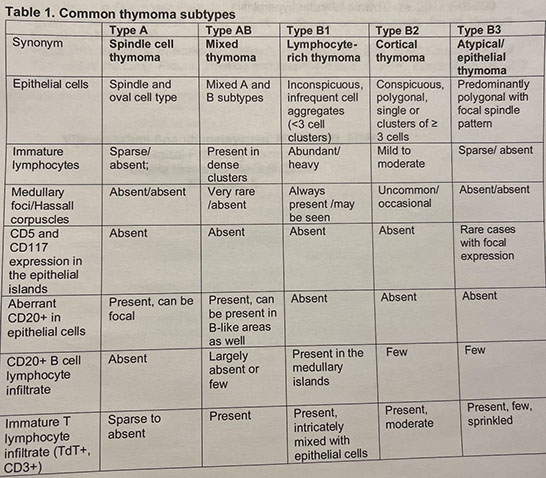

Histologically subclassified as A, AB, or B1-B3, based on "organotypical" features (i.e. histologic resemblance to normal thymic development)

- Mixed patterns may occur within the same tumor, necessitating the need for adequate sampling

-- Recommended to classify thymomas with heterogenous patterns by the predominant pattern, followed by the minor components in 10% increments

Type A and AB is more spindly cells

-- most type AB have focal immature lymphocytes (thymocytes, type-B like) and focal lymph poor areas (type A-like)

- B1-B3 more epithelioid

-- B1 has more lymphs and less epithelioid cells, B3 has less lymph and more epithelioid cells

- B2 intermediate, with some epithelial cell clusters

-- medullary islands essentially req'd to dx type B1

Variant called micronodular thymoma, c spindly cells in compact swirled nodules, usually mature (CD20+) B-cells

IHC: thymocytes (immature lymphs) + for CD99, CD1a and TdT; epithelial cells CK / p63+

- negative CD5 and CD117 (vs thymic carcinoma)